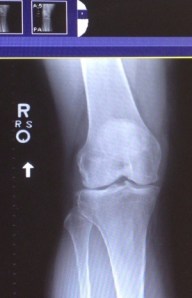

I went to the sports medicine doctor on Friday, and he had a good laugh about my coming in two weeks before the Tinman knowing full well I would not skip it. In fact, I told him I wanted to come in the day after but I was in too much pain now. So he set me up with a diagnosis, provided me with exercises, made me promise I’d ice it every day, and he prescribed shoe inserts because I’m flat footed. I run with a mid-foot strike. Believe it or not, the knee doesn’t hurt that much when I run. It’s AFTER. And when I walk it goes all boingy and hyper extends. For that reason he says I should use elevated slippers and shoes with a moderate heel for day-to-day footwear. OK! He also said he doesn’t think I should do the marathon readiness series, but to prepare at my own pace, which is slower than that. He also threw in how he’s thinking about doing the Tinman. Kids these days!